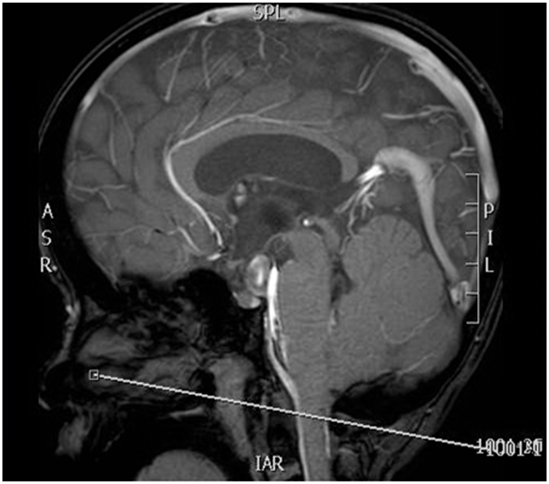

Page the radiologist to plan and place the axial cine sequence. The positioning will depend on the patient anatomy, but it will generally be in this area (see image below). Feel free to set it up and send the rads a screenshot of what you have done. Images must be checked.

| SAG CINE | PCA- VENC 5 | FFE | 10mm | 0mm | None | 18cm | MSP- Centered on Foramen Magnum |

| SAG CINE | PCA- VENC 12 | FFE | 10mm | 0mm | None | 18cm | MSP- Centered on Foramen Magnum |